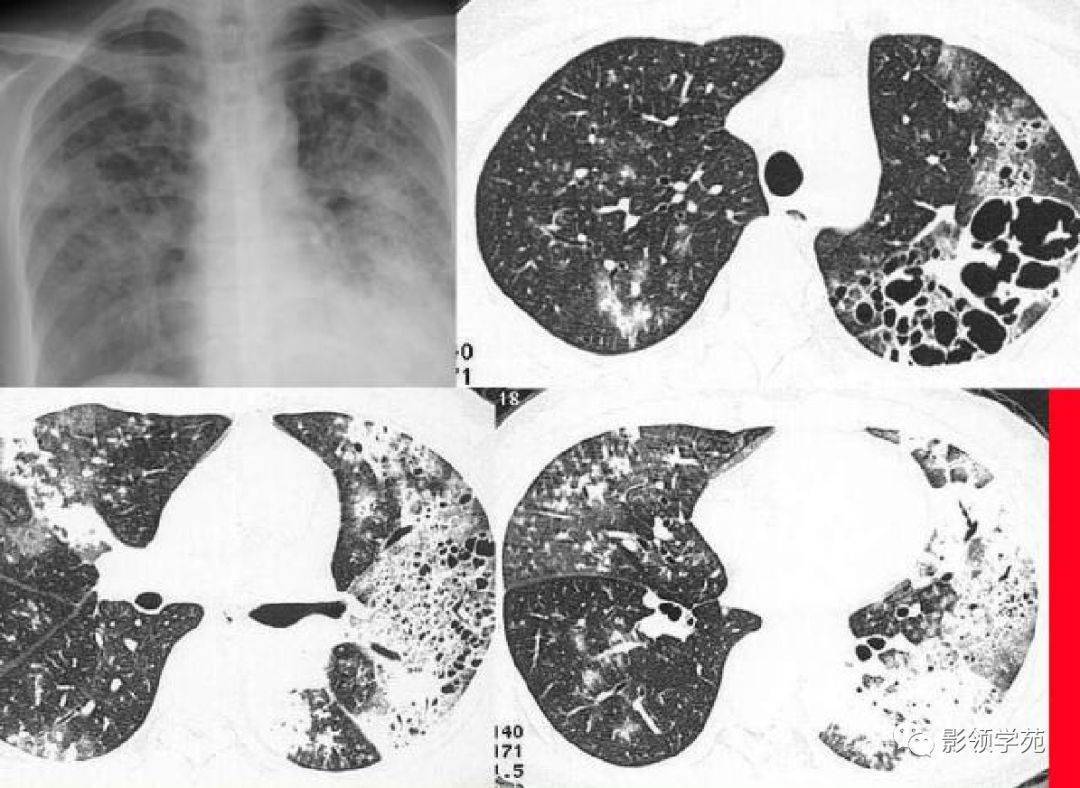

肺空洞是一种常见的疾病,它在肺部形成了一个孔洞。这个孔洞通常由于感染引起的肺组织坏死而形成。最常见的原因是结核菌感染,但也可能与其他细菌、真菌或寄生虫感染有关。当感染侵袭肺部时,免疫系统会试图清除感染,但有时会导致肺组织死亡,并形成空洞。

肺空洞的症状各异,包括持续咳嗽、咳出血痰、胸痛以及呼吸困难。然而,有些人可能没有任何明显的症状。要确诊肺空洞,医生通常会进行一系列检查,包括胸部X射线、CT扫描和支气管镜检查。这些检查可以帮助医生确定肺部是否存在空洞,并排除其他可能的疾病。